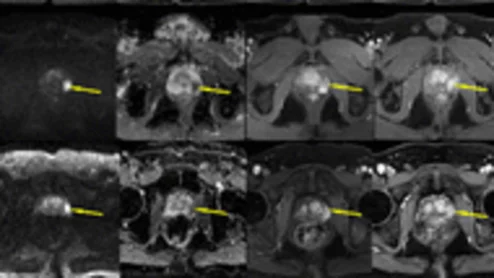

The less invasive method could help men avoid some of the unpleasant side effects such as urinary incontinence and sexual dysfunction, which are known deterrents for patients facing potential prostatectomy.

Simulated MR images could eliminate the need for contrast in prostate scans.

Synthetic images are often of diagnostic quality and can be reliably used to assess clinically significant prostate cancer while also sparing patients from contrast exposure.